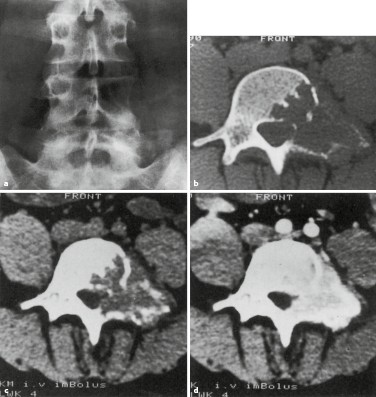

Primare Und Sekundare Knochengeschwulste Springerlink